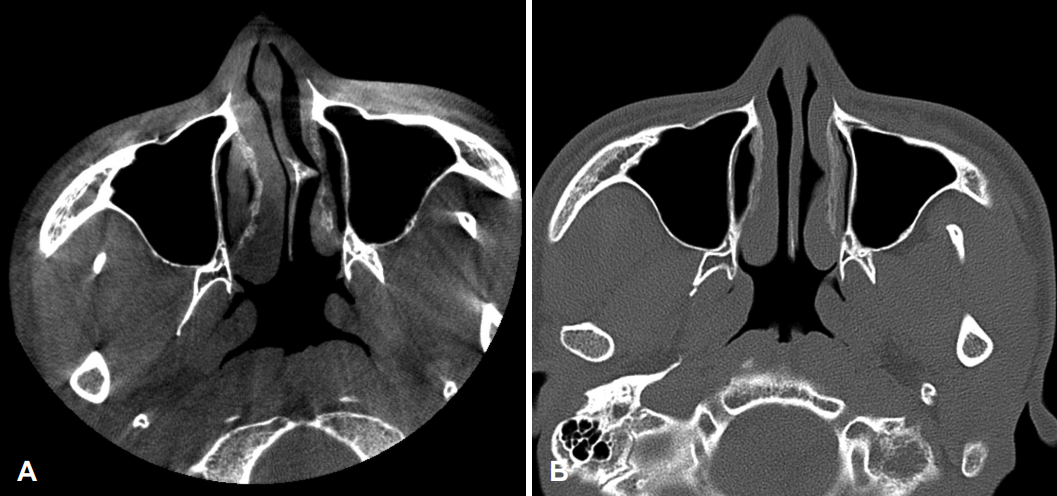

특이 병력이 없는 24세 남자 환자가 1년 전부터 발생한 우측 비폐색 및 간헐적인 수양성 비루, 후비루를 주소로 내원하였다. 비내시경 소견상 좌측으로 편향된 비중격 만곡 및 돌출된 비중격 돌기(septal spur)가 관찰되었고 좌측 하비갑개는 돌출된 비중격 돌기로 인해 함몰되어 있었다(Fig. 1). 타원에서 촬영했던 cone beam CT상에서도 좌측으로 편향된 비중격 및 좌측으로 돌출된 비중격 돌기를 확인할 수 있었으며 부비동염은 관찰되지 않았다(Fig. 2A). 피부 단자 검사는 음성 소견으로 확인되었고, 음향 비강 통기도검사상 좌측 비강이 하강하는 W 모양으로 우측에 비해 좁아져 있는 소견이 확인되었다(Fig. 3A). 상기 소견을 종합해보았을 때 좌측으로 편향된 비중격 만곡증 및 우측의 보상성 하비갑개 비대로 인한 비폐색으로 진단하였으며, 이에 대해 비중격 수술을 계획하였다.

CT image of the patient. A: CT finding before septoplasty showed left septal deviation with dimpled inferior turbinate. B: Postoperative CT demonstrated showed straightened septum with persisting dimple on the left inferior turbinate.

해당 약제를 약 1개월 반 사용한 뒤 재평가를 시행하였으나 환자는 여전히 호흡과 연관된 목의 건조감 및 통증을 심하게 호소하였다. CT 검사를 새로 시행한 결과 좌측 비중격 돌기가 제거되어 비중격의 좌측 편향은 호전되어 있었으나 하비갑개의 용적과 위치에는 뚜렷한 차이점이 관찰되지 않았다(Fig. 2B). 음향 비강 통기도검사상 점막 수축 미시행 시 좌측에 하강하는 W 모양의 비밸브 협착이 여전히 확인되었으나 수술 전 콧구멍으로부터 2.8 cm 떨어진 위치에 존재하였던 2nd minimal cross-sectional area (MCA)부터는 수술 전에 비해 비강 내 용적 확장이 이루어진 것이 관찰되었다(Fig. 3B).

그러나 본 증례에서는 하비갑개의 용적 축소가 이루어지지 않았으며, 하비갑개 전단에 위치한 내비밸브의 단면적 변화 또한 없었다. 비강 통기도 검사상 내비밸브를 의미하는 첫 번째 MCA는 수술 전 콧구멍에서 1.56 cm 거리에 위치하였으며 면적은 0.46 cm2였고, 수술 후에 콧구멍으로부터 1.43 cm 거리에 0.43 cm2의 면적으로 측정되어 수술 전과 큰 차이를 보이지 않았다. 두 번째 MCA는 수술 전에는 콧구멍에서 2.77 cm 거리, 면적 0.66 cm2로 측정되었으나 수술 후에는 콧구멍에서 4.32 cm 거리, 면적은 1.24 cm2로 측정되었는데, 수술 전에 비중격의 돌기로 인해 형성되었던 두 번째 MCA가 수술 후 콧구멍으로부터 약 4 cm 거리에 위치하는 일반적인 두번째 MCA인 중비갑개의 전단부위로 바뀌었음을 시사한다. 즉, 본 증례에서 해부학적 구조 변화는 비갑개가 아닌 비중격의 교정에 의해 주로 발생하였음을 알 수 있다.